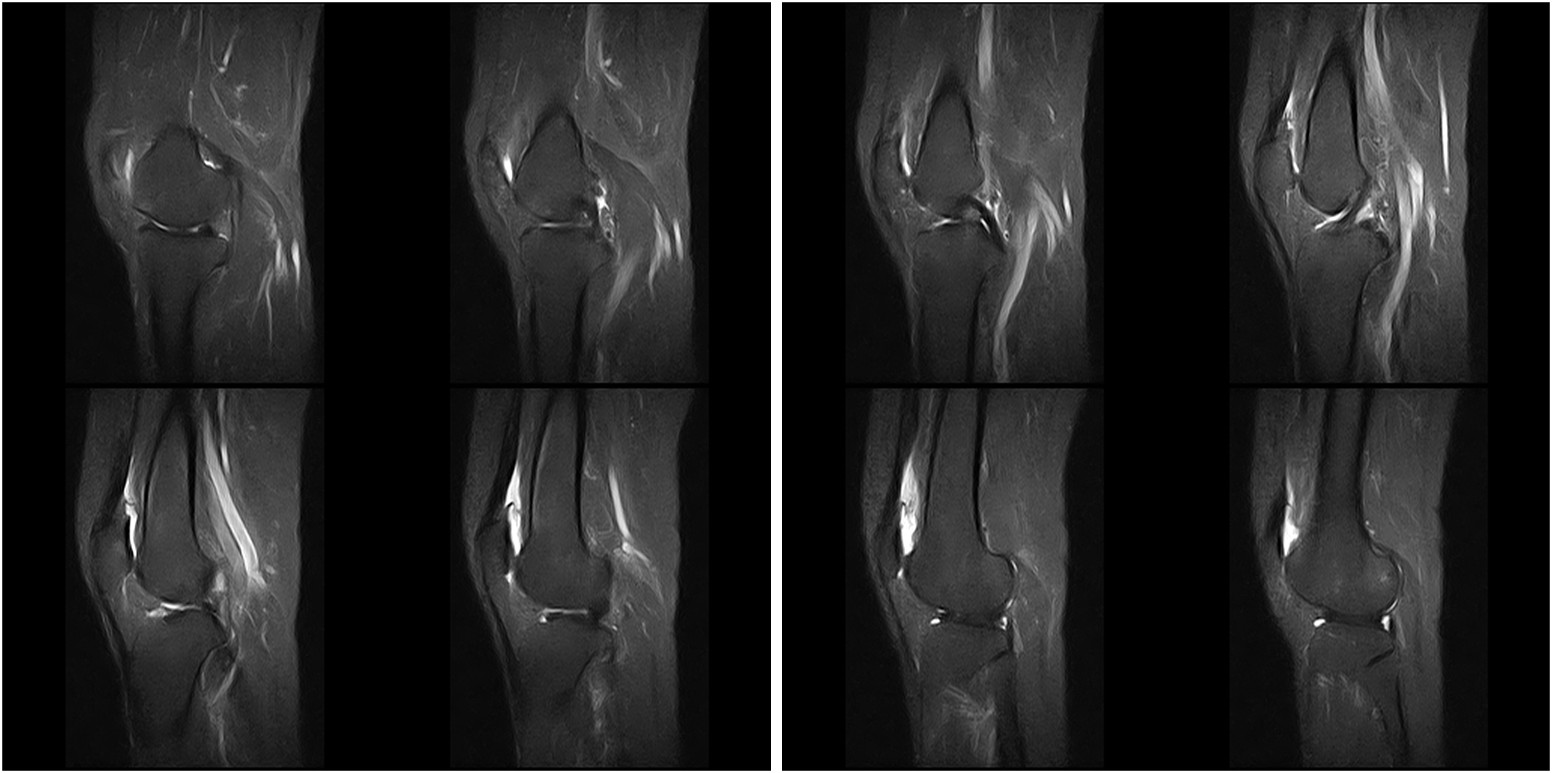

Hình ảnh lâm sàng

Giải pháp lâm sàng ấn tượng